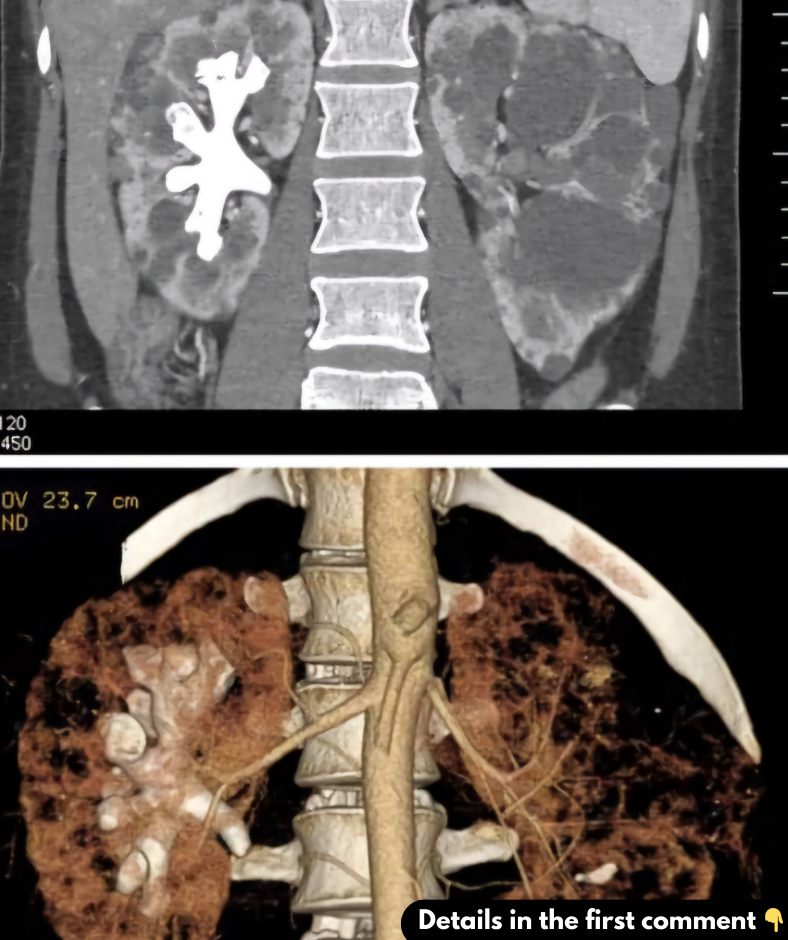

Staghorn kidney stones get their name from their distinctive antler-like appearance. These stones are not only large but also branch into the kidneyโs cavities like a deerโs antlers, filling the renal pelvis and extending into the calyces. Typically made of a compound called struvite, these stones are often a result of repeated urinary tract infections and are more prevalent in women.

One of the biggest challenges posed by staghorn stones is their size and intricate location within the kidney, making them less likely to pass naturally. If not surgically removed, they can cause substantial damage to the kidney, emphasizing the need for early diagnosis and prompt treatment.